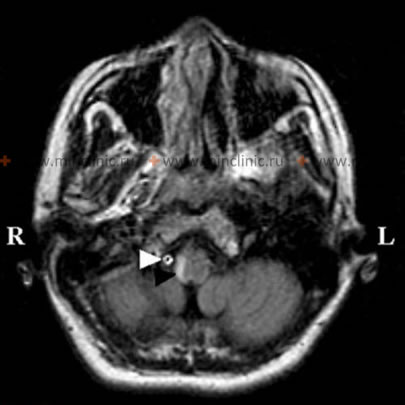

- თავის ტვინის მრტ: არჩევის ვიზუალიზაციის მეთოდი. დიფუზია-შეწონილი ვიზუალიზაციის (DWI) რეჟიმები ძალიან მგრძნობიარეა მწვავე იშემიის გამოსავლენად წუთებიდან საათებში, ნათლად აჩვენებს ინფარქტებს მოგრძო ტვინსა და ნათხემში. FLAIR რეჟიმები ეხმარება ინფარქტის ხანდაზმულობის შეფასებაში, ხოლო GRE/SWI რეჟიმებს შეუძლიათ გამოავლინონ მცირე სისხლჩაქცევები ან დისექციის ნიშნები.

| ლატერალური მედულარული სინდრომი (იშემიური ინსულტი) | კლასიკური კონსტელაცია: ვერტიგო, ნისტაგმი, იპსილატერალური ატაქსია, დისფაგია/ხმის ჩახლეჩა, იპსილატერალური სახის და კონტრალატერალური სხეულის ტკივილის/ტემპერატურის დაკარგვა, ჰორნერის სინდრომი. უეცარი დასაწყისი. | მრტ (DWI) ადასტურებს მწვავე ინფარქტს ლატერალურ მოგრძო ტვინში +/- ქვედა ნათხემში. სისხლძარღვოვანი ვიზუალიზაცია (კტა/მრა/დსა) ავლენს ხერხემლის არტერიის/PICA-ს ოკლუზიას/სტენოზს/დისექციას. |